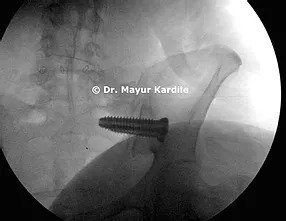

A 55-year-old lady complained of chronic low back radiating to left buttock pain for 6 years. Her pain was so severe that it didn't even allow her to roll in bed or climb upstairs without discomfort. Her life was clearly limited due to this pain.

A clinical diagnosis of SI joint dysfunction was made. Not having relief after two SI joint injections, she was advised Minimally invasive (MIS) SI joint fusion surgery.

MIS SI joint fusion is done through a 3 cm incision in the buttock area. In carefully selected patients, this procedure can give gratifying results.